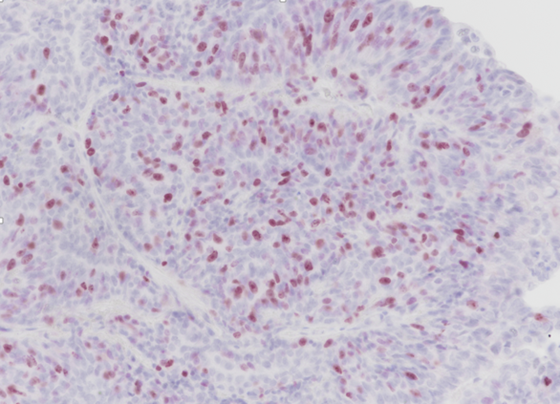

Cane Femmina intera 9,6 anni. Carcinoma solido della mammella. Immunoistochimica -  Ki67 (x20).